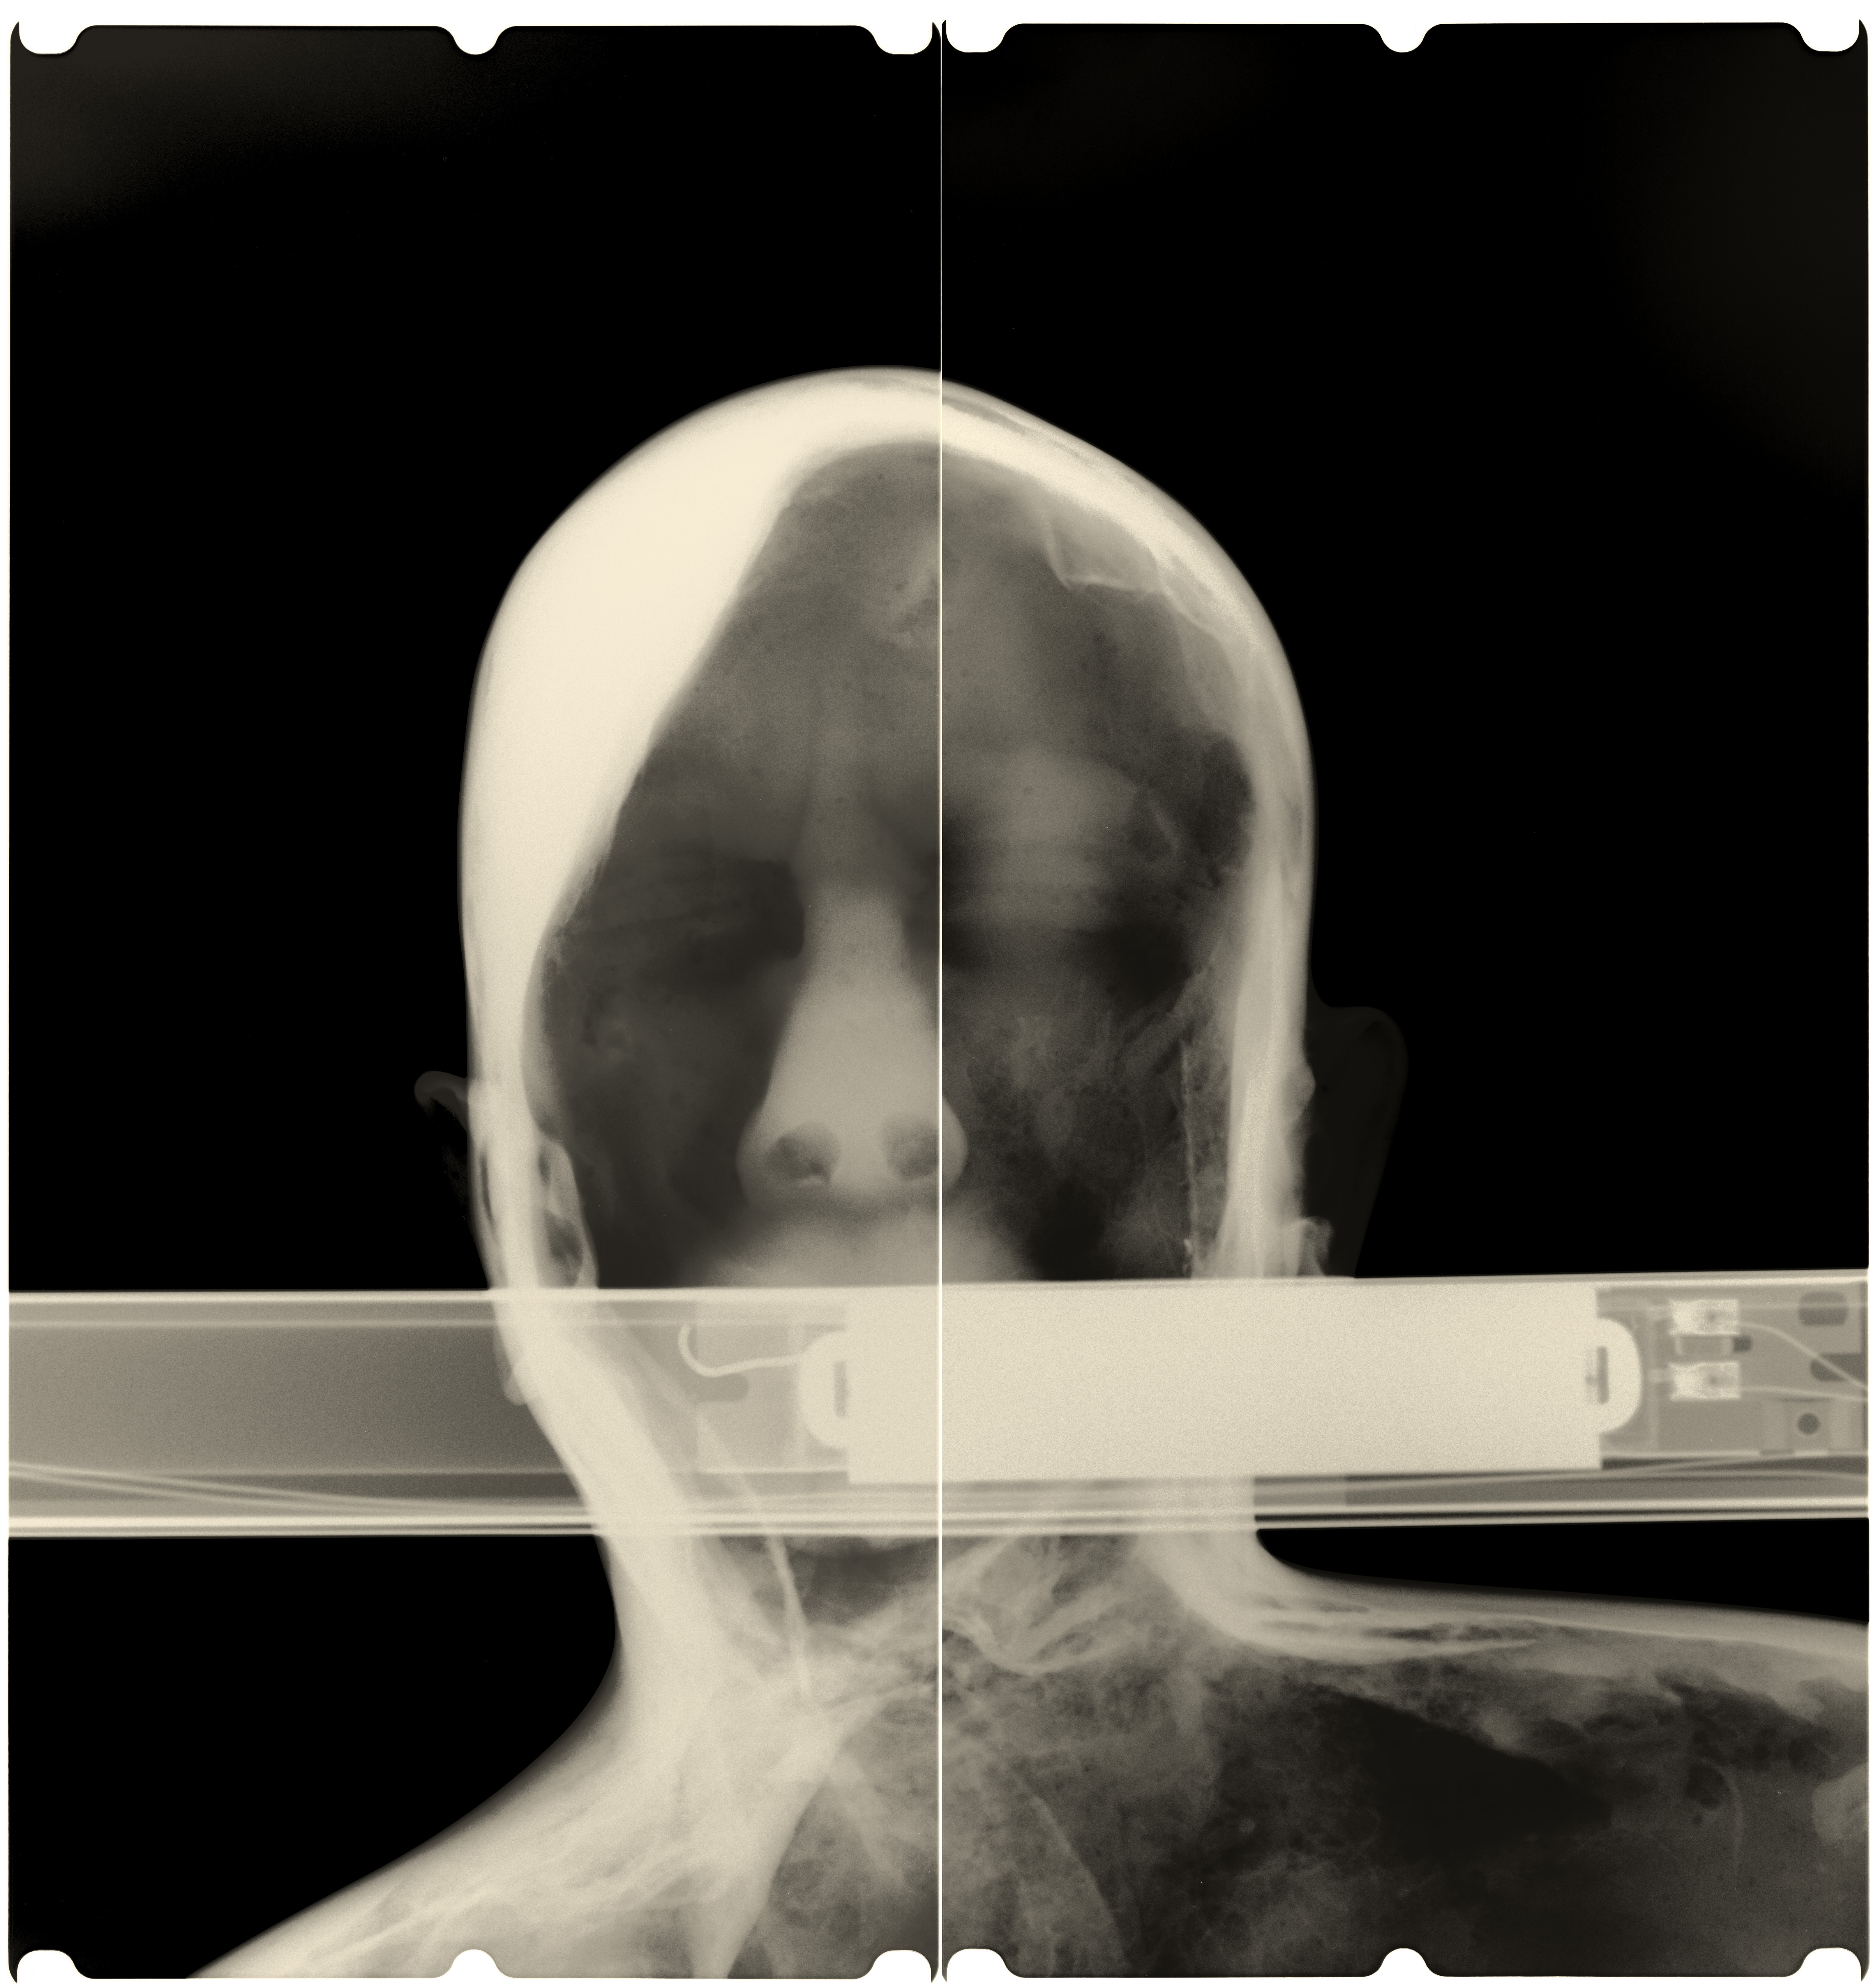

Artifacts of Evidence / Dokazno gradivo je prostorska instalacija umetniških del studia Paul O Robinson v dialogu s knjigo-artefaktom umetnice in oblikovalke Maje Licul. Preobraženim objektom in prostorom iz hiše Jožeta Plečnika so sopostavljena dela, ki izhajajo iz kontinuiranega raziskovanja interierjev in eksterierjev v Sloveniji in Italiji – v slednji natančneje v muzeju Fortuny v Benetkah. Postavitev se ukvarja z vprašanji stalnosti in minljivosti ter preoblikovanja konvencionalnih znakov v nove snovne oblike. Rentgenska dokumentacija je pretvorjena v slikarske in kiparske forme, pri čemer se skrita vsebina razgrinja v nove prostorske strukture.